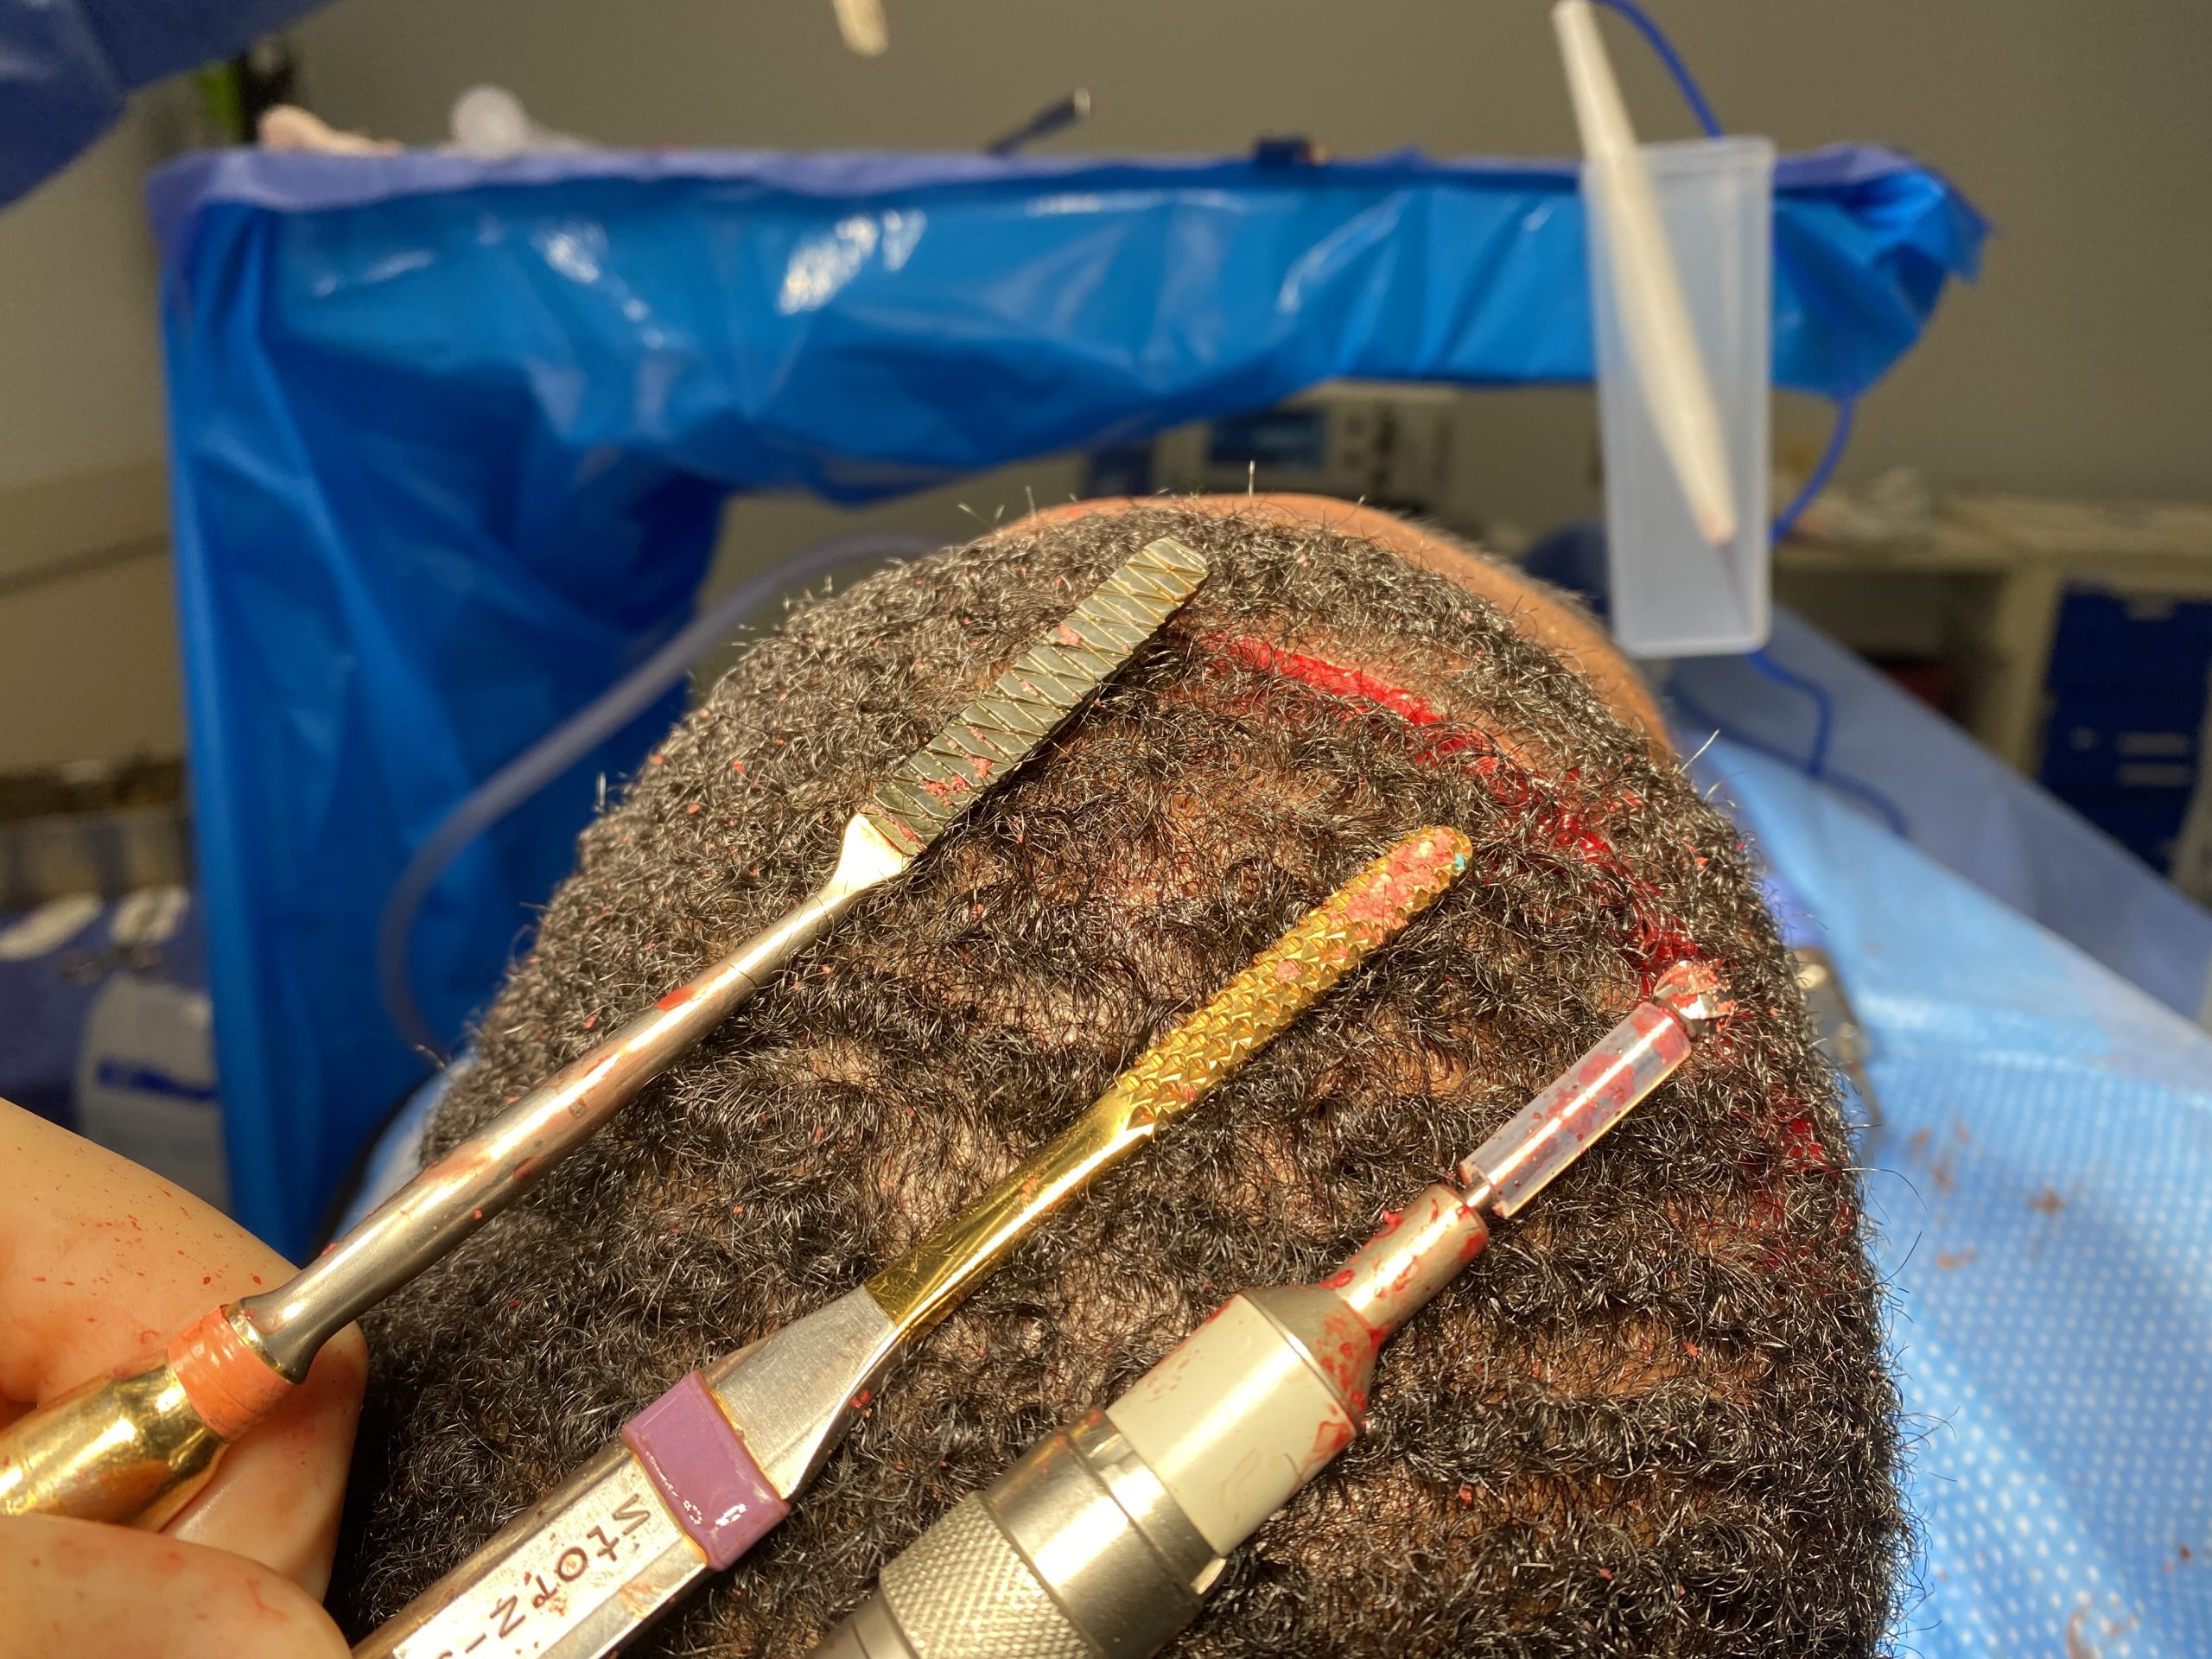

Patient 47

Desire for reduction of prominent occipital knob deformity.

Intraoperative result from occipital knob skull reduction through a direct small scalp incision.

Desire for reduction of prominent occipital knob deformity.

Intraoperative result from occipital knob skull reduction through a direct small scalp incision.